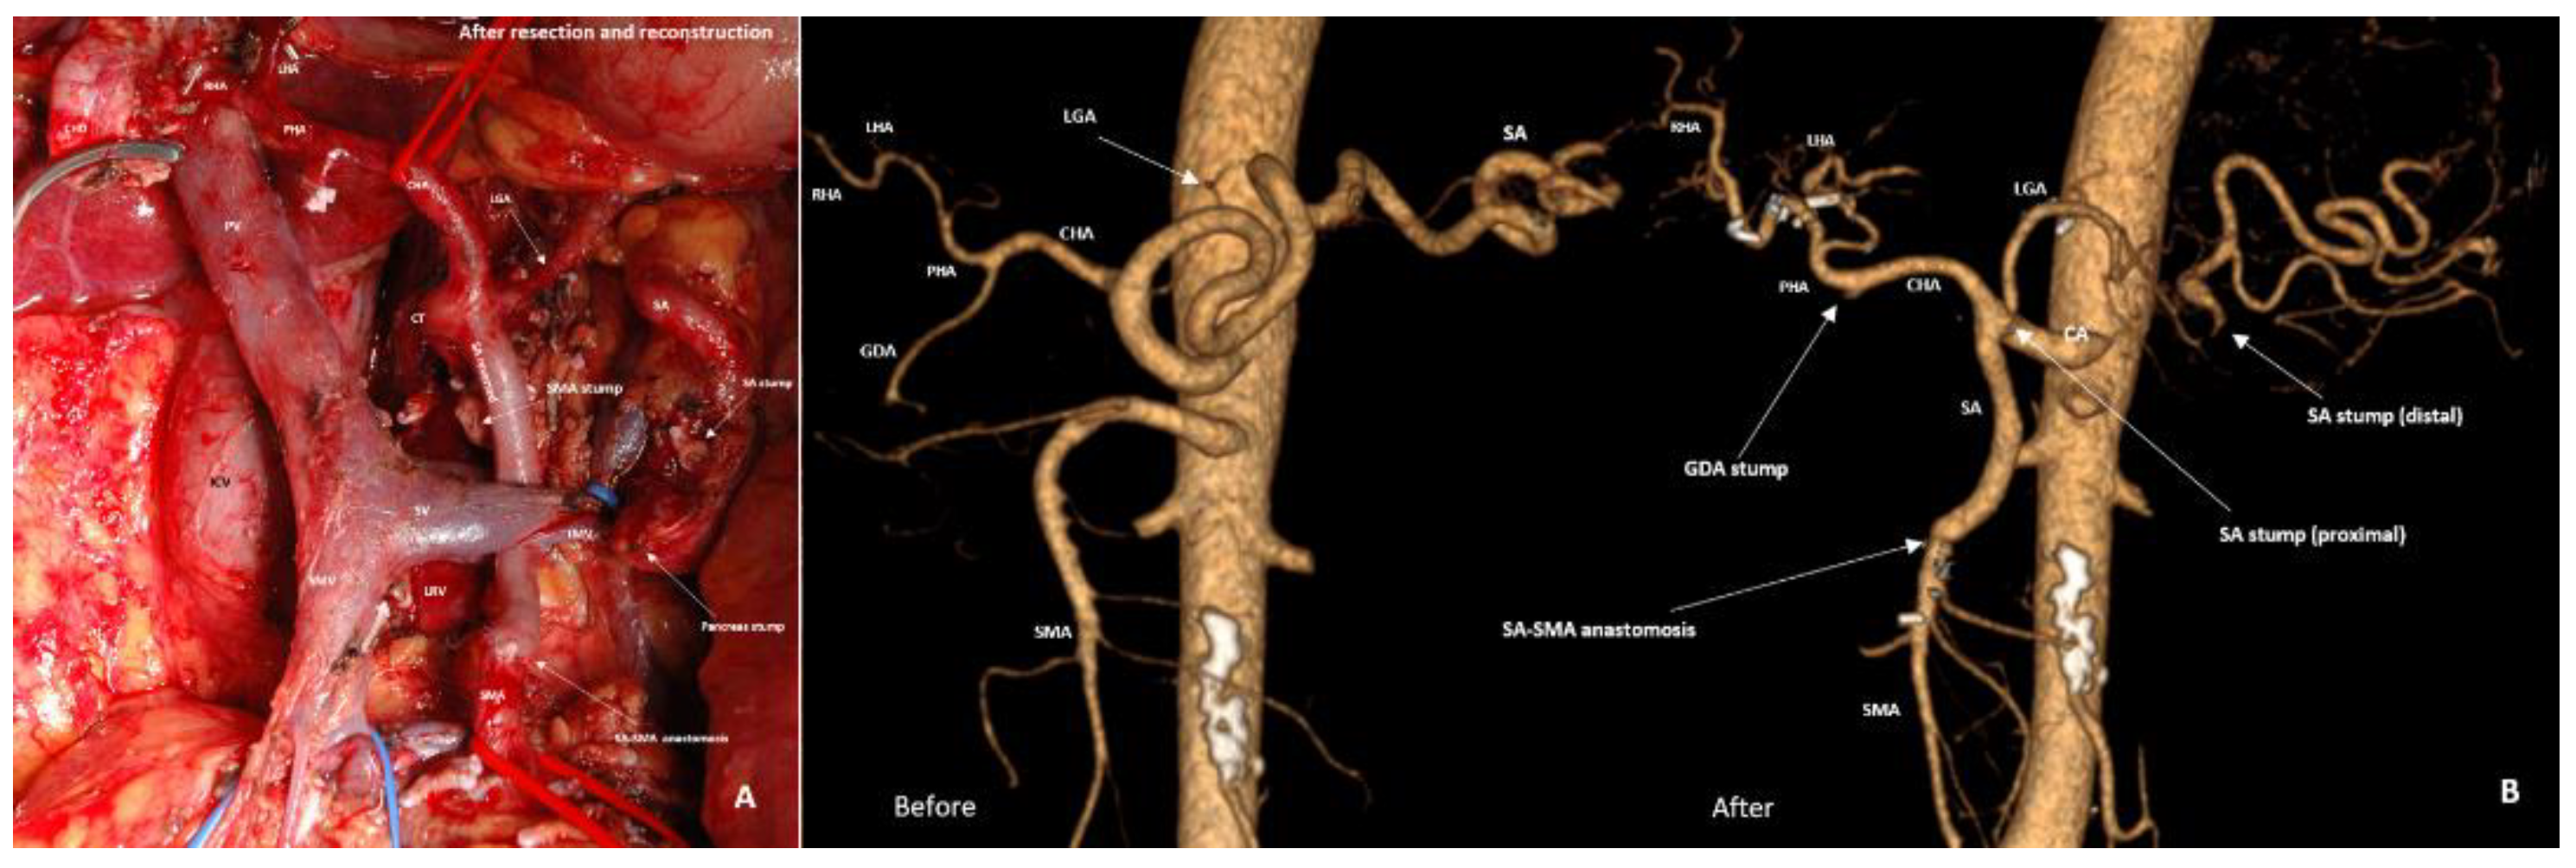

3.3. Spleen-Preserving Pancreatectomies with Resection of the Splenic Vessels, Other than Distal Resections

3.4. Spleen-Preserving Pancreatectomies with Resection of the Splenic Artery (Vessels) for Border Line Resectable and Locally Advanced Pancreatic Head Cancers